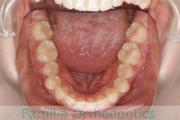

No.22V-409

- 叢生

- 16歳

- 女性

- 抜歯部位

- 上:

- 44

- 下:

- 8|58

- 主な使用装置:

- FEA

- 治療にかかった費用:

- 86万円

八重歯を治したいということで来院されました。下あごの左ずれのある上顎前突(出っ歯)・叢生(でこぼこ)でしたので、上は左右から、下はで左のみ小臼歯を抜歯して、歯科矯正用アンカースクリューとマルチブラケット法にて治療を行いました。2年強、30回程度の通院が必要でした。

上下とも前歯の叢生(でこぼこ、凹凸、ガタガタ)があるため、保定を怠ると後戻りのリスクがあります。

- ≫治療前

上顎

下顎

- ≫治療後